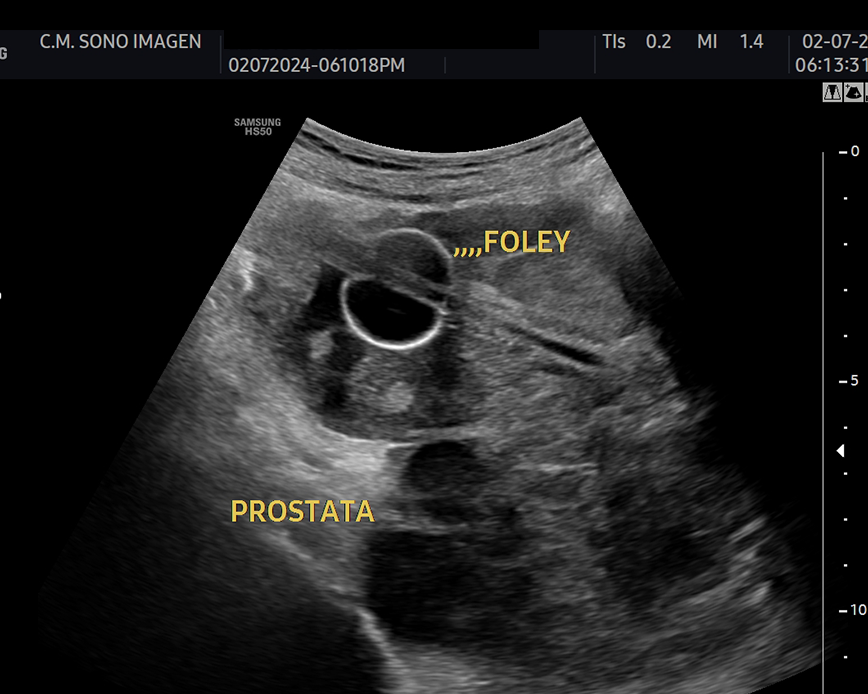

Ecografía Prostática

- hiperplasia prostática benigna(HPB)

- dificultad para orinar o retención urinaria

- control postquirúrgico o postratamiento